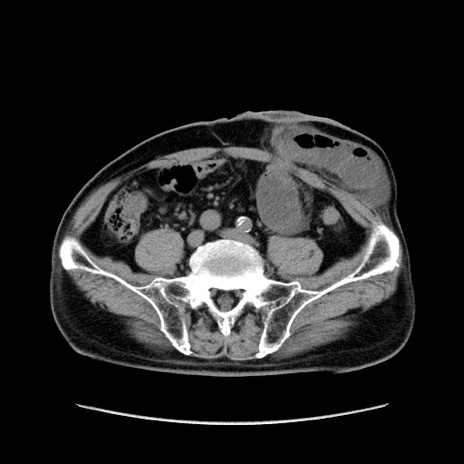

症例24(横断像)

【症例】80歳代男性

【主訴】左側腹部痛、嘔吐

【現病歴】本日早朝より左腹部に痛みあり。昼頃嘔吐認めたため、救急要請。

【既往歴】直腸癌(Mile手術)、胆摘

【身体所見】意識清明、BT 35.9℃、BP 221/93mmHg、SpO2 97%(RA) 、腹部:左ストーマ周囲に限局性の腹部膨隆あり。 膨隆部自発痛・圧痛あり・軟。

【データ】WBC 7700、CRP 0.09